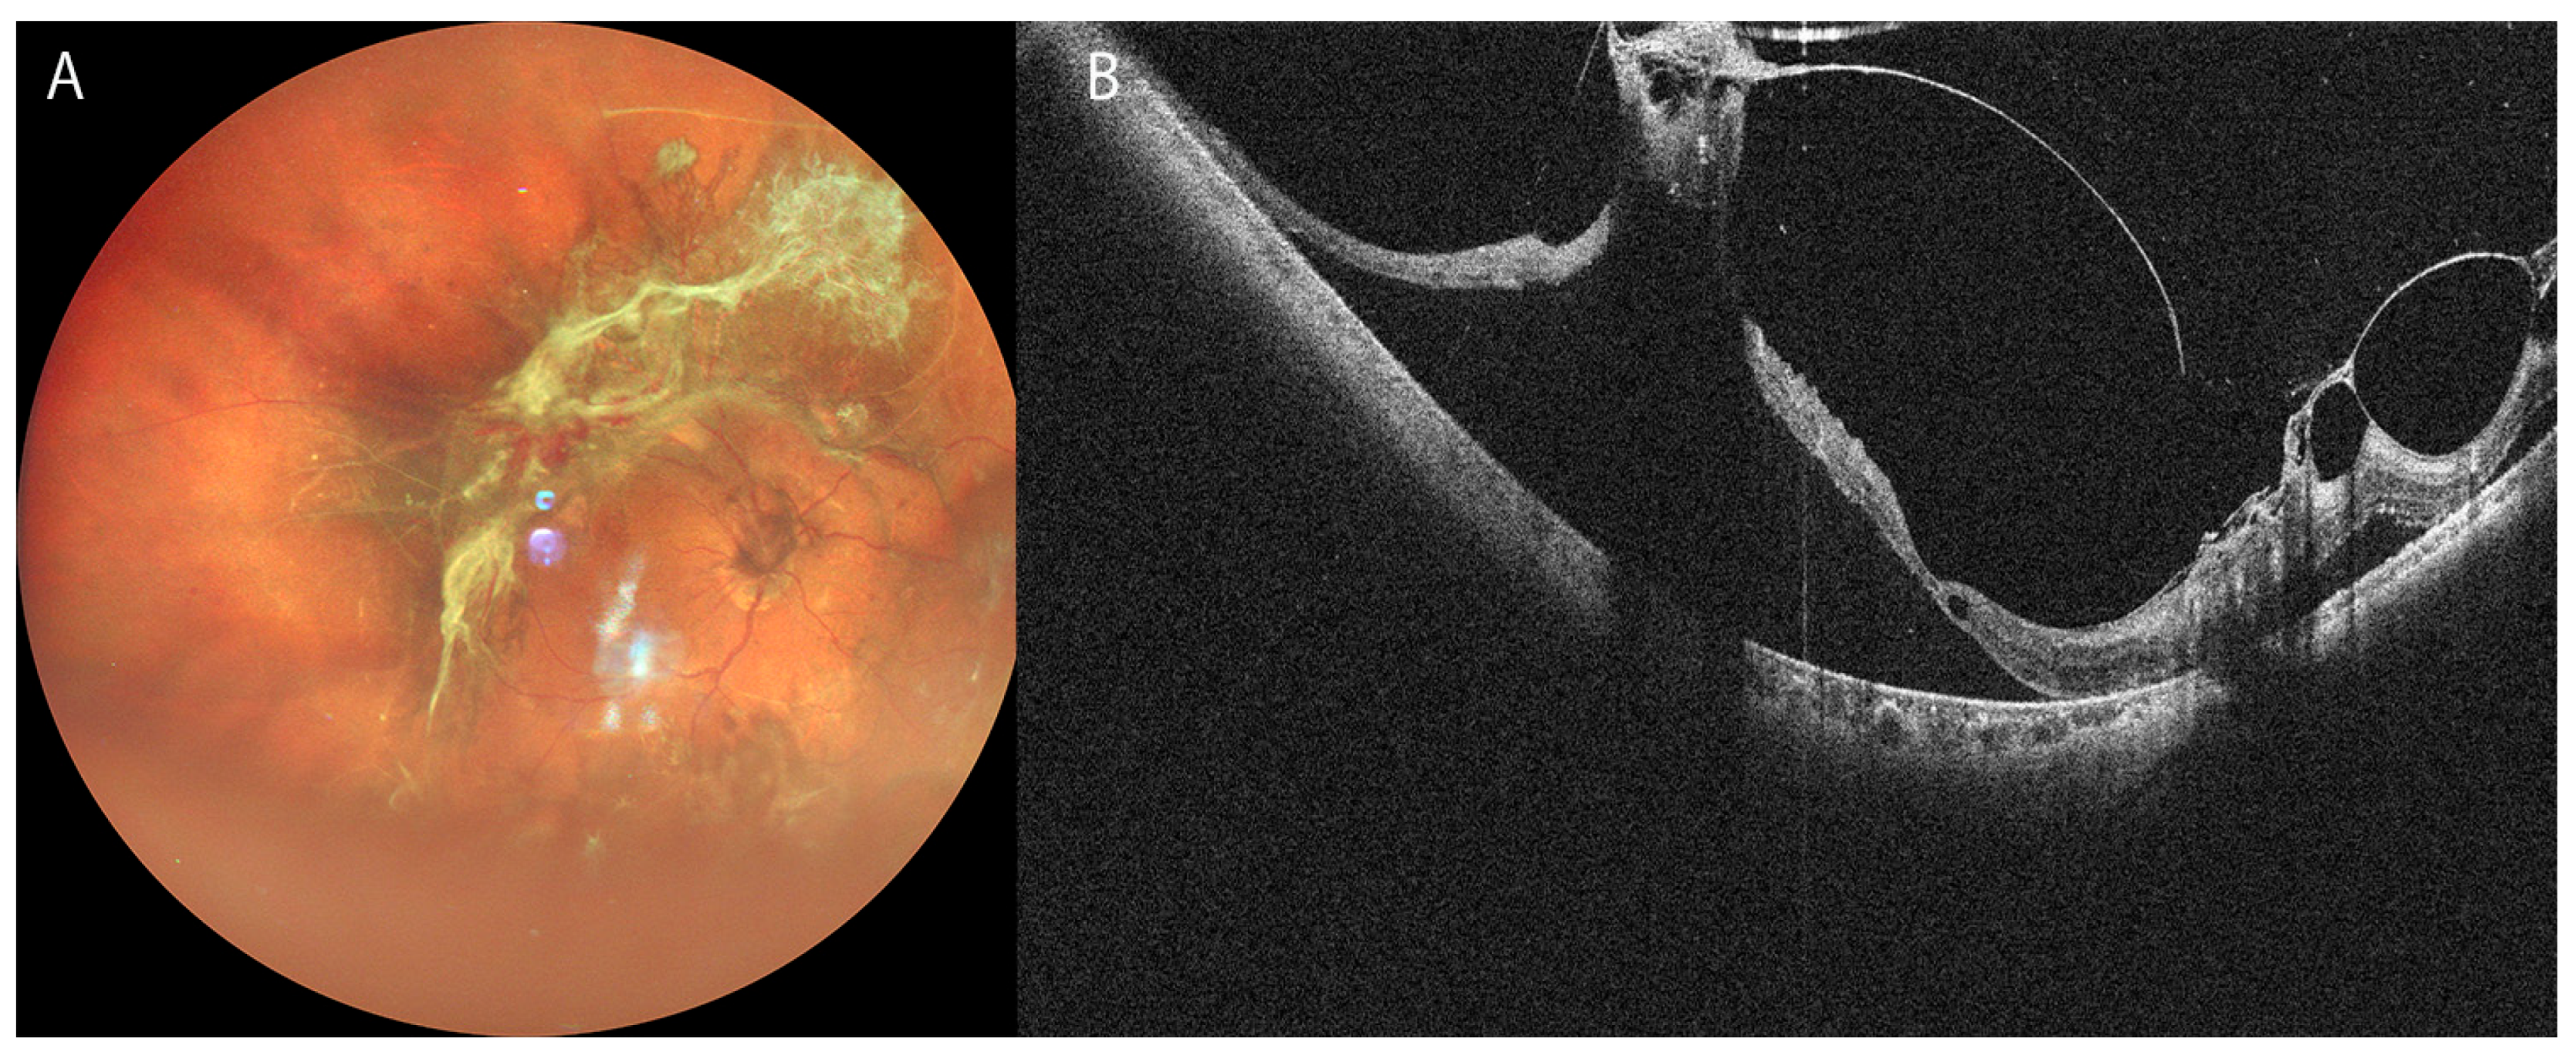

3.2. Retinal Detachment

- Takahashi, H.; Uramoto, K.; Ohno-Matsui, K. Ultra-Widefield Optical Coherence Tomography For Retinal Detachment With Proliferative Vitreoretinopathy. Retin. Cases Brief. Rep. 2022, 16, 355–359. [Google Scholar] [CrossRef] [PubMed]

- Martins Melo, I.; Bansal, A.; Naidu, S.; Oquendo, P.L.; Hamli, H.; Lee, W.W.; Muni, R.H. Morphologic Stages of Rhegmatogenous Retinal Detachment Assessed Using Swept-Source OCT. Ophthalmol. Retin. 2023, 7, 398–405. [Google Scholar] [CrossRef]

- El-Sehemy, A.; Martins Melo, I.; Pecaku, A.; Zajner, C.; Naidu, S.; Motekalem, Y.; Muni, R.H. Postoperative Photoreceptor Integrity and Anatomical Outcomes Based On Presenting Morphologic Stage Of Rhegmatogenous Retinal Detachment. Retina 2024, 44, 756–763. [Google Scholar] [CrossRef] [PubMed]

- Martins Melo, I.; Naidu, S.; Pecaku, A.; Zajner, C.; Bansal, A.; Oquendo, P.L.; Lee, W.W.; Muni, R.H. Impact of Baseline Morphologic Stage of Rhegmatogenous Retinal Detachment on Postoperative Visual Acuity. Ophthalmol. Retin. 2024, 8, 624–632. [Google Scholar] [CrossRef]